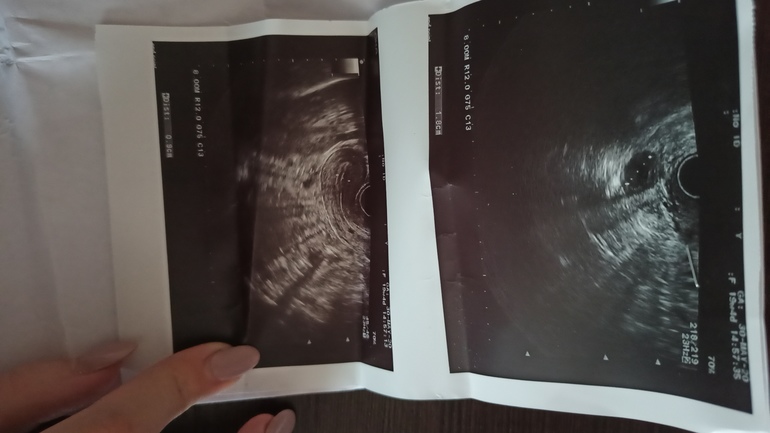

А вот О я так и не поняла когда. Хотя 30.05 я была на УЗИ и мне сказали, что вот вот должен лопнуть фоликул. По ощущениям совпало конечно.

Но все же, до этого 28 у меня были похожие и я запуталась. А когда посмотрела на фото УЗИ, у меня возник вопрос, а не могла ли узистка перепутать ДФ с ЖТ?

На снимке ДФ. Уже овальный, готовый лопнуть. О была либо ночью, либо на след.день.